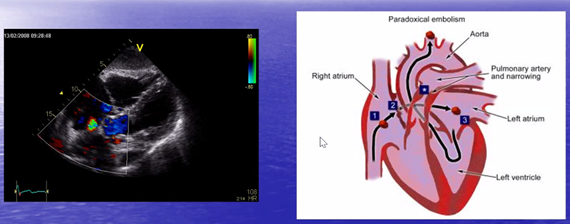

Men varför fick mannen symptom med talsvårigheter och vänstersidig svaghet?

Den djupa ventrombosen kan embolisera framför allt till lunga men det finns ibland en shunt (foramen ovale) som gör att det kan nå systemkretsloppet direkt

När vi tar i, eller när vi behöver kräkas eller tar i mer på muggen. Då kan trycket bli högre i vensystemet som gör att höger förmak som gör att det övergår till vänster förmak genom foramen ovale